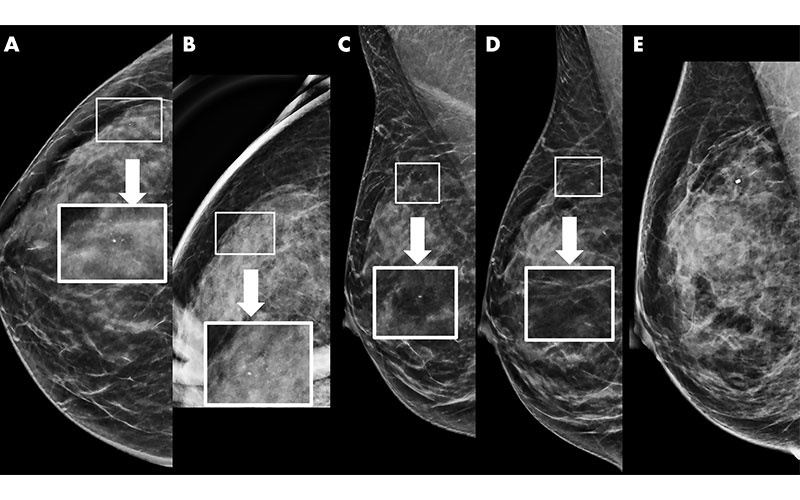

Example of synthetic imaging calcification enhancement in a 43-year-old woman who presented for screening. A, Screening mammogram obtained with synthetic imaging (craniocaudal view). New faint amorphous calcifications are seen in the outer breast. Finding was classified as Breast Imaging Reporting and Data System (BI-RADS) category 0. Inset image was obtained at ×3 magnification. B, Diagnostic mammogram, two-dimensional magnification view (craniocaudal view), confirms the presence of calcifications; however, they are of equal or less conspicuity compared with that seen with synthetic imaging. Inset image was obtained at ×3 magnification. Finding was classified as BI-RADS category 4. C, Screening mammogram obtained with synthetic imaging (mediolateral oblique view). New faint amorphous calcifications are seen in the superior breast. They are less conspicuous compared with those on the craniocaudal view in A. Finding was classified as BI-RADS category 0. Inset image was obtained at ×3 magnification. D, Diagnostic digital mammogram obtained at recall (mediolateral view). Calcifications are much less conspicuous on two-dimensional digital mediolateral view. Inset image was obtained at ×3 magnification. Finding was classified as BI-RADS category 4. E, Diagnostic mammogram obtained with two-dimensional imaging after biopsy (digital mediolateral view). The clip is in appropriate location. Pathologic examination showed ductal carcinoma in situ, intermediate grade.

https://doi.org/10.1148/radiol.2020200240 ©RSNA 2022

According to the authors, synthetic mammography (SM) was developed to decrease the radiation dose to women undergoing DBT. SM is not meant to be an exact replica of digital mammography. The reconstruction algorithm purposefully enhances areas, such as calcifications and potential areas of architectural distortion, to make them more conspicuous to the radiologist.